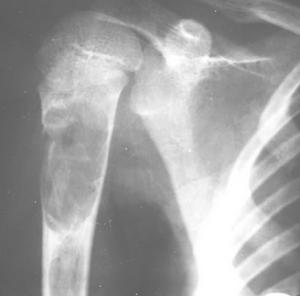

骨囊腫X線平片位於長骨幹骺端,呈圓形、卵圓形或柱形,沿長骨縱軸發展,表現為輕度膨脹性生長,局部骨皮質變薄,邊緣光整,無骨膜增生。合併病理骨折時,骨碎片向囊內移位,稱“碎片陷落征”,有助於鑑別。

有經驗的骨腫瘤醫生僅憑X線平片就可以作出骨囊腫的臨床診斷。病變灶為邊界清晰的液性低密度灶,四壁為薄層的硬化灶殼。病變灶略向近骨骺的乾骺部位擴大。病灶非偏心性,也不破壞骨外殼,更不會突破骨質形成骨膜外反應骨,除非是在病理骨折後的癒合期。有時脫落的骨皮質成份落入囊腔中,X片顯示被稱為“落葉征”(FallenleaforFallenfragment)。當病灶發生在骨盆,CT掃描對病灶部位及囊腫形態的判斷有價值。MRI可以明確囊內富含的液性成分。骨ECT掃描表現為外周薄的濃集而中央病灶冷區。